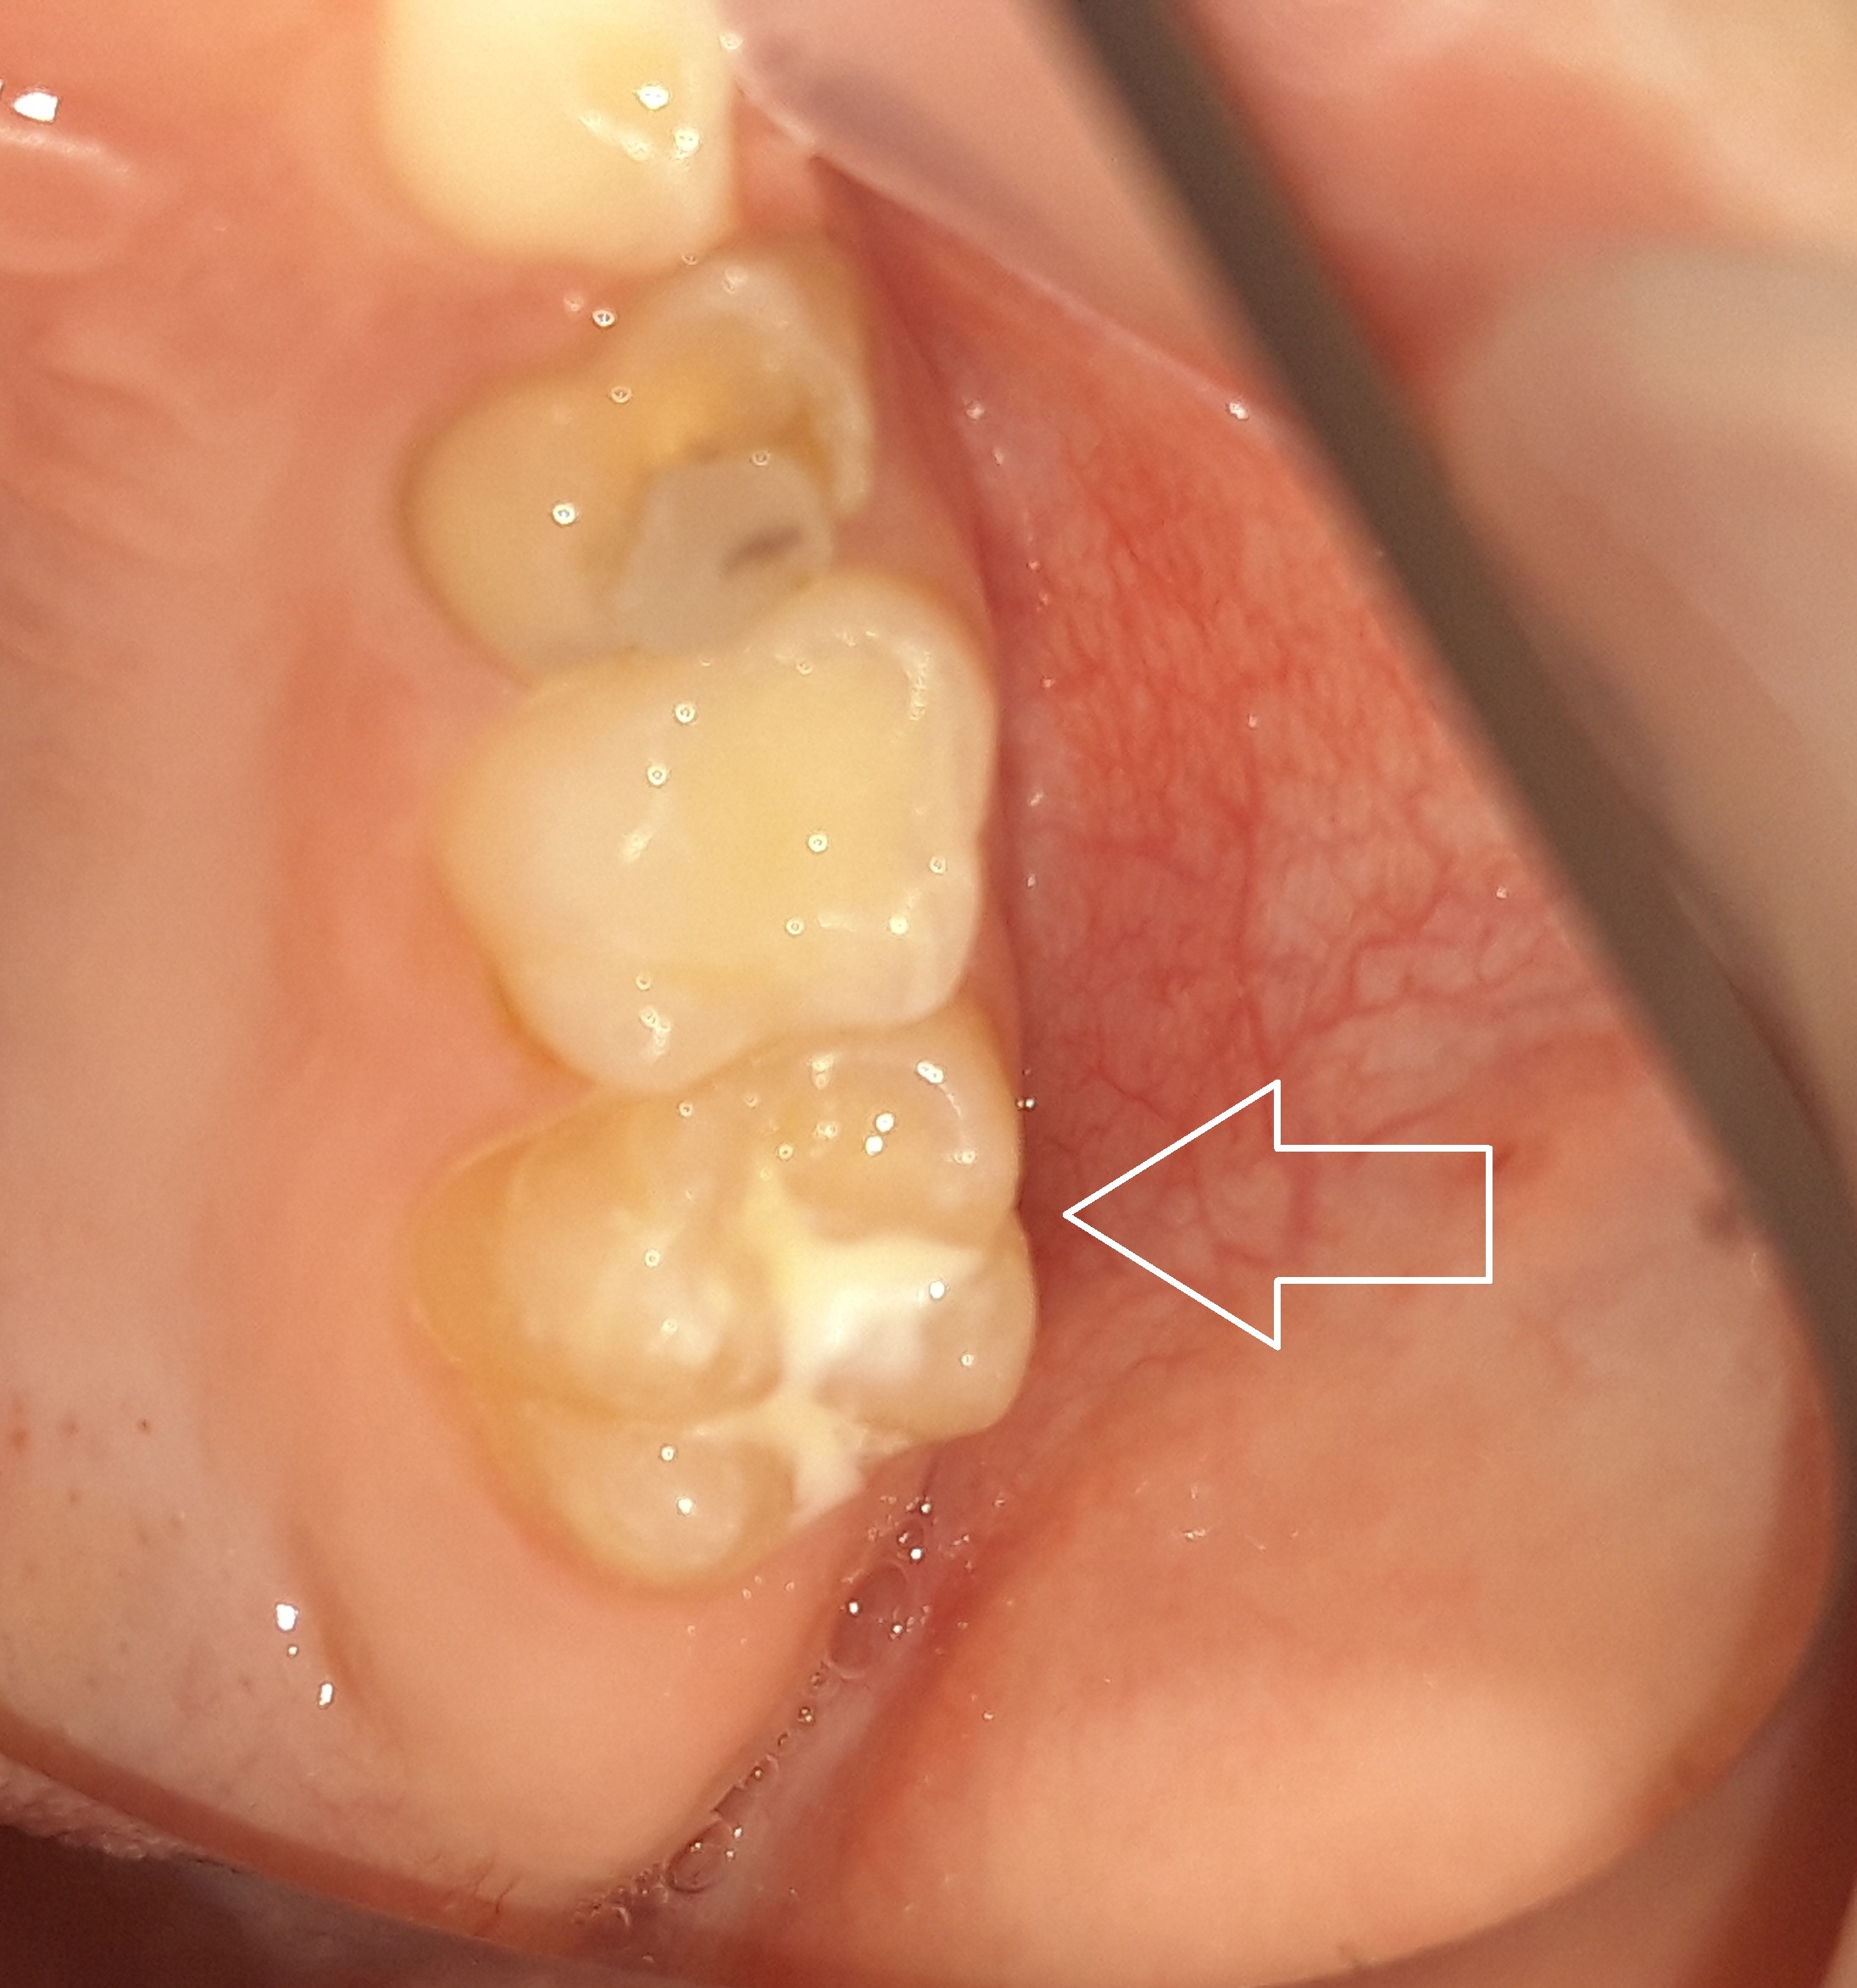

Στο συγκεκριμένο ασθενή πραγματοποιήθηκε ταυτόχρονα αφαίρεση της επιφανειακής αρχόμενης τερηδόνας και προληπτική κάλυψη οπών και σχισμών (sealant) στη μασητική επιφάνεια του άνω αριστερού πρώτου γομφίου.

Περιστατικά – Sealant / προληπτική κάλυψη οπών και σχισμών